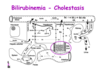

Bilirubinemia - Cholestasis

- Break down of RBCs is normal, the hepatocytes will conjugate the bilirubin

- there is blockage: bilirubin in the blood and in the urine

Bilirubinuria